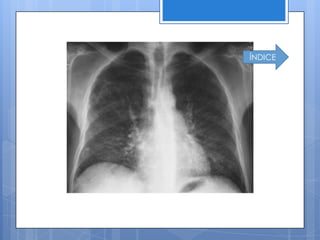

Radiografía de tórax

 Revelaprotrusión de la arteria pulmonar

principal y aumento en la anchura de la

rama descendente de la arteria

pulmonar derecha.

 Enenfermedad venooculsiva se aprecian

Líneas B de kerley, cuando hay ausencia

de datos de insuficiencia del ventrículo

izquierdo.

ÍNDICE